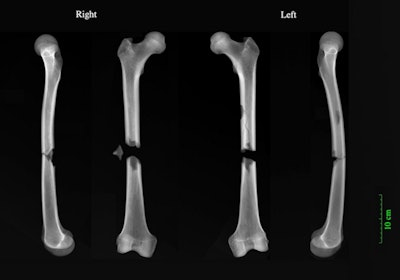

X-rays of perimortem butterfly fractures to both femora of an adult male (PSN 531) buried in the Augustinian friary, Cambridge. All images courtesy of Reveal Imaging and Jenna Dittmar, PhD."By comparing the skeletal trauma of remains buried in various locations within a town like Cambridge, we can gauge the hazards of daily life experienced by different spheres of medieval society," said Jenna Dittmar, PhD, study lead author from the After the Plague project at the university's department of archaeology. "We can see that ordinary working folk had a higher risk of injury compared to the friars and their benefactors or the more sheltered hospital inmates."

"The friar had complete fractures halfway up both his femurs," said Dittmar in a press release. "Whatever caused both bones to break in this way must have been traumatic, and was possibly the cause of death. Our best guess is a cart accident. Perhaps a horse got spooked and he was struck by the wagon."